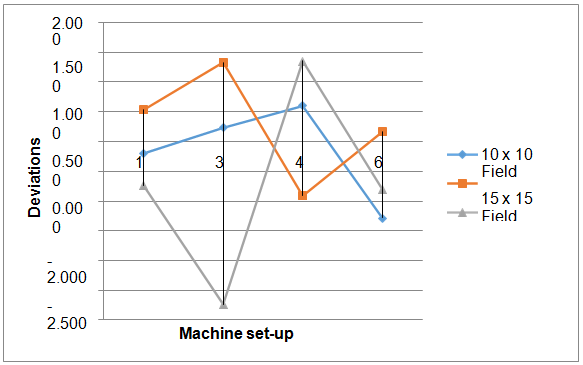

After calculating wedge angles we determine the deviations between calculated angles and machine set-up angles by subtracting calculated angles from machine set-up angles in degrees then finally calculated the percent deviation. The Figure 2 shows the percent deviation between machine set-up angles and calculated angles for 6 MV energy. This shows that the deviation is independent of machine set-up angles and field sizes the deviation in this case within 4 %. The Figure 3 shows the percent deviation between machine set-up angles and calculated angles for 15 MV energy. This shows that the deviation is independent of machine set-up angles and field sizes, the deviation in this case within 3 %. The variation or deviation in 15 MV is lesser than 6 MV it is may be due to beam hardening effect in 6 MV, beam hardening is the effect when radiations passes through from metal low energy captured in metal. The previously study was done on PRIMUS3008 linear accelerator Siemens and the deviation between calculated and machine set-up angle is found to be within 1%.16 The recent study regarding the wedge angle confirmation for Elekta for 15° 15 cm2 field size is given in Table 3.17 Our study shows the deviations from original value within 3 % ,which is acceptable this variation increases in higher fields due to the electron contamination with x-rays beam ,deviation also increases with wedge angle as thickness increases energy decreases. As far as the effect of energy beam is concerned ,in low energy deviation increases due to the beam hardening effect.

Figure 3 Deviation between calculated and machine set-up angles at various field sizes for 15 MV energy.